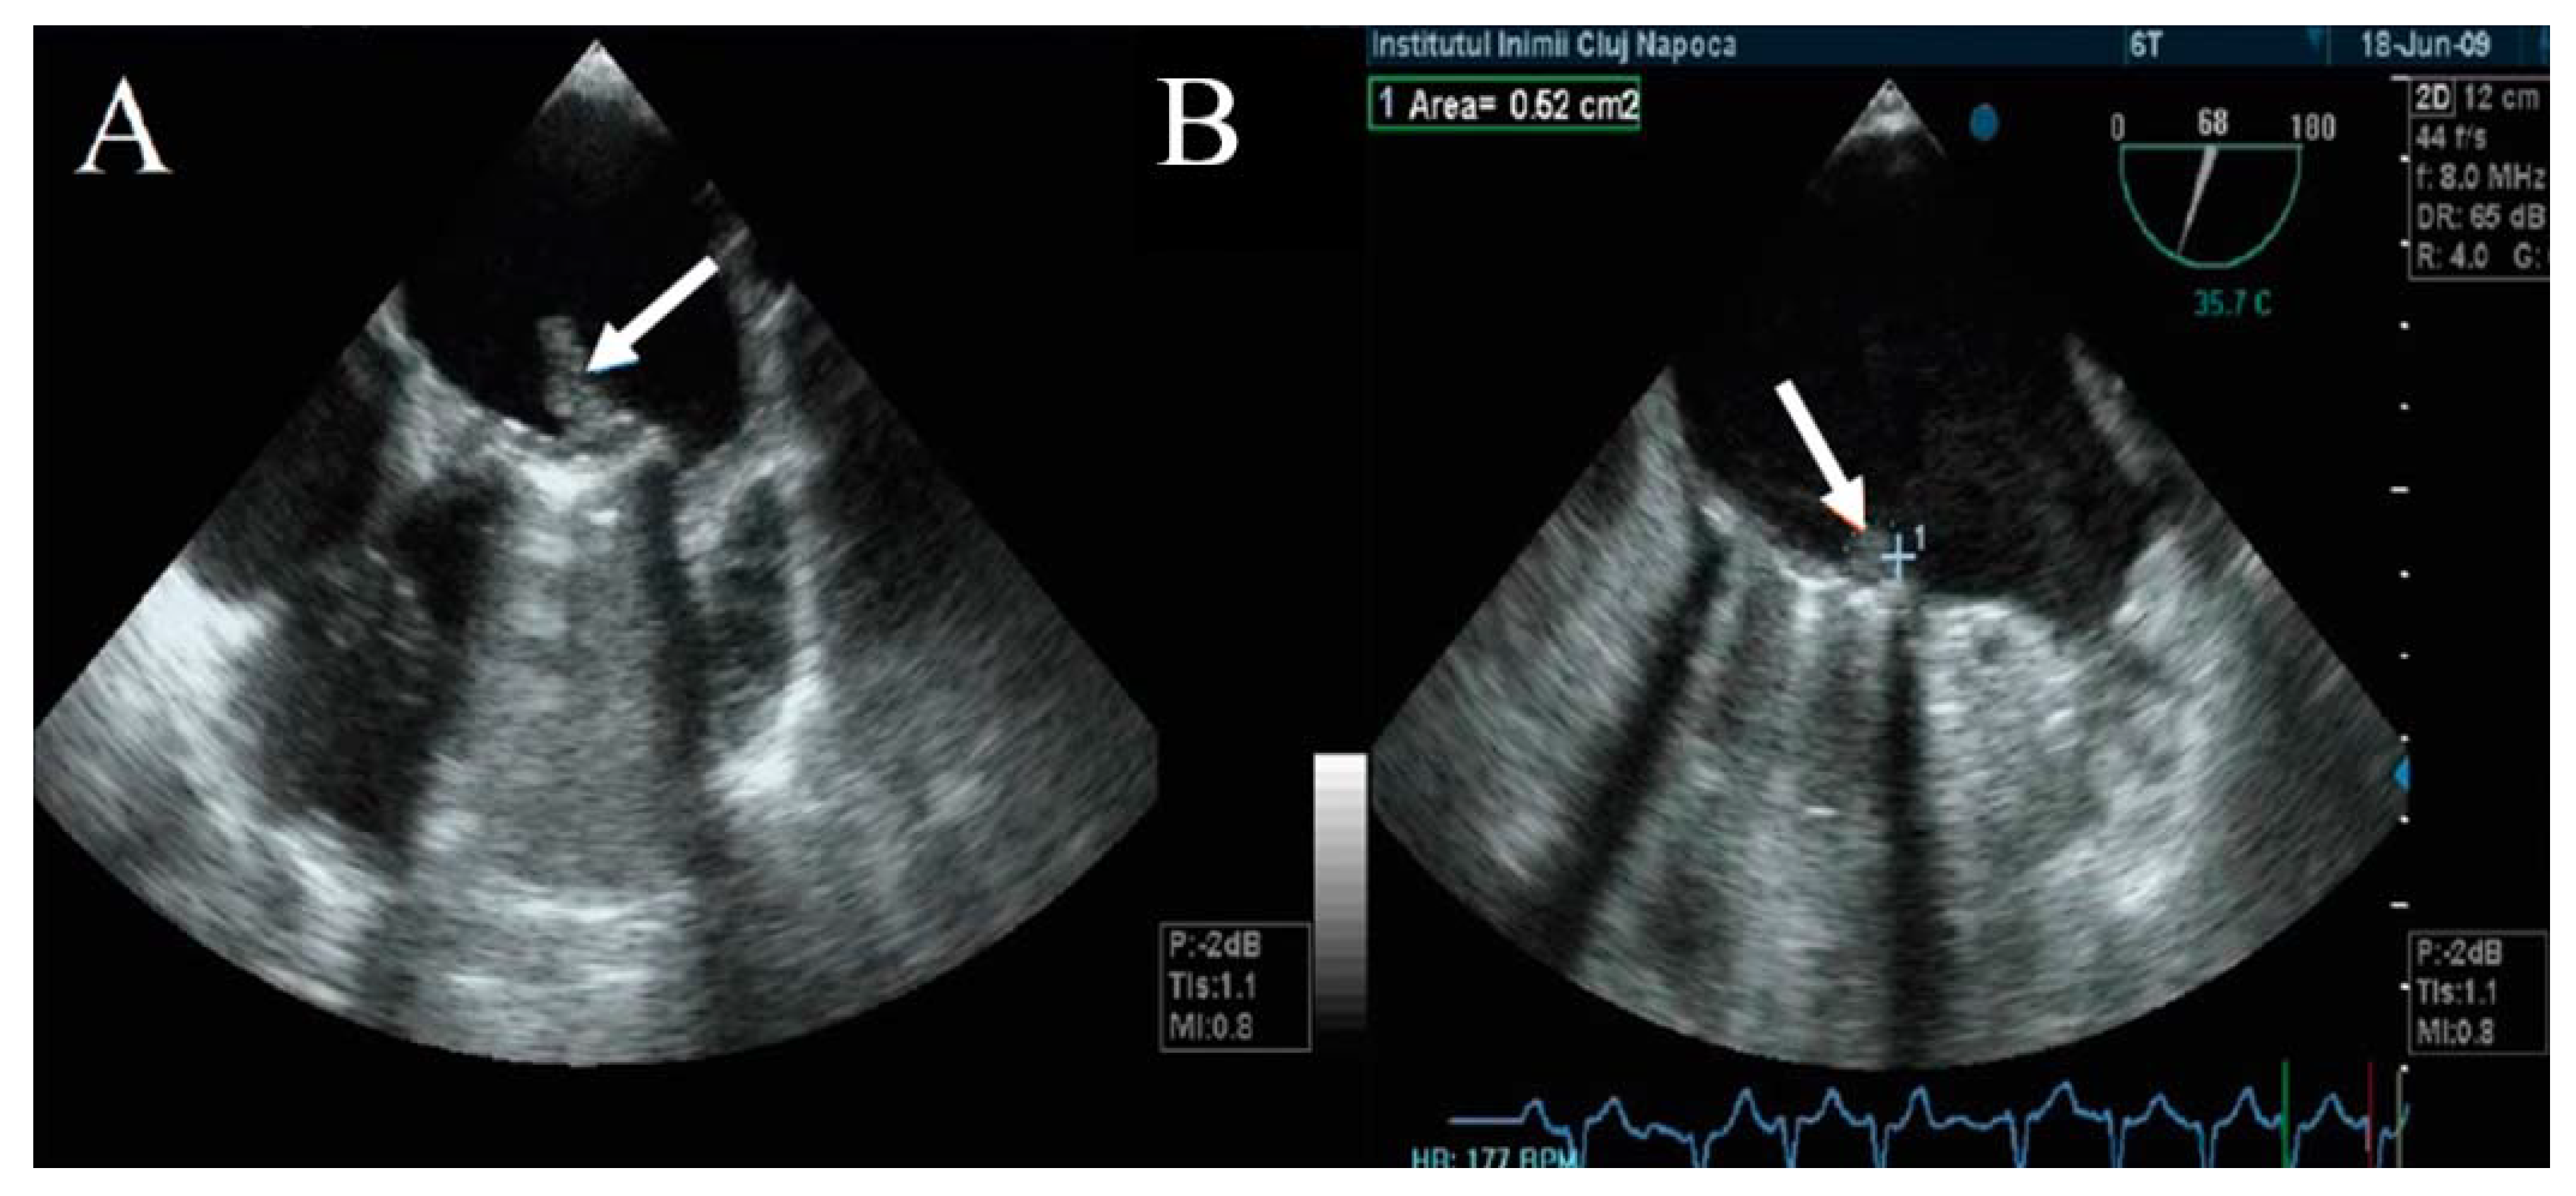

TEE has a major role in describing the size, mobility, and thrombus extension. It also has the ability to describe whether the thrombus is obstructive or nonobstructive, an essential aspect in the choice of therapeutic management (Figure 5) [1,21,22,25,27,28,29,30,31,32].

Figure 5.

TEE. Obstructive thrombus on the atrial side of mechanical mitral prosthesis (arrow).

The thrombus can be viewed as a polylobulated, amorphous mass with an echo density equal to the myocardium, an irregular contour, and variable movement that restricts the mobility of the prosthetic discs (Figure 6). The thrombus size defines the severity of the prosthesis obstruction. Generally, a recent onset of symptomatology with hypermobile obstructive thrombi is associated with hemodynamic instability and high embolic risk [21,22,23,24]. Tong et al. reported that a thrombus on left heart prosthesis with an area below 0.8 cm2 is associated with a lower risk of death, as well as embolic events after thrombolytic treatment [34].

Figure 6.

TEE. Obstructive huge thrombus on the atrial side of mechanical mitral prosthesis extended in left atrium appendix.

Moreover, Ozkan M. et al. reported that a thrombus area above 0.9 cm2 that generates obstruction of the left heart prostheses increases the risk of embolism or death associated with a thrombolytic treatment. Based on this, the 2014 ACC/AHA guideline recommends emergency surgical treatment when the size of the thrombus on the left heart prosthesis is over 0.8 cm2. Thrombolytic treatment is recommended when the size of the thrombus is below 0.8 cm2, with a recent onset of symptoms and NYHA class I–II [10].

The embolic risk depends not only on the thrombus area, but also on the mobility and echogenicity of the thrombus. A recent onset of symptomatology and hypermobile thrombi with reduced echogenicity have a higher embolic risk than those that are hyperechogenic with reduced mobility (Figure 7) [35]. Moving images of floating thrombi on mitral prostheses are illustrated in Video S3 (Supplementary Material).

Figure 7.

(A) TEE. Nonobstructive thrombus with high embolic risk (fresh, hypermobile) on the mitral prosthesis. (B) TEE. Small, immobile thrombus on the mitral prosthesis ring.